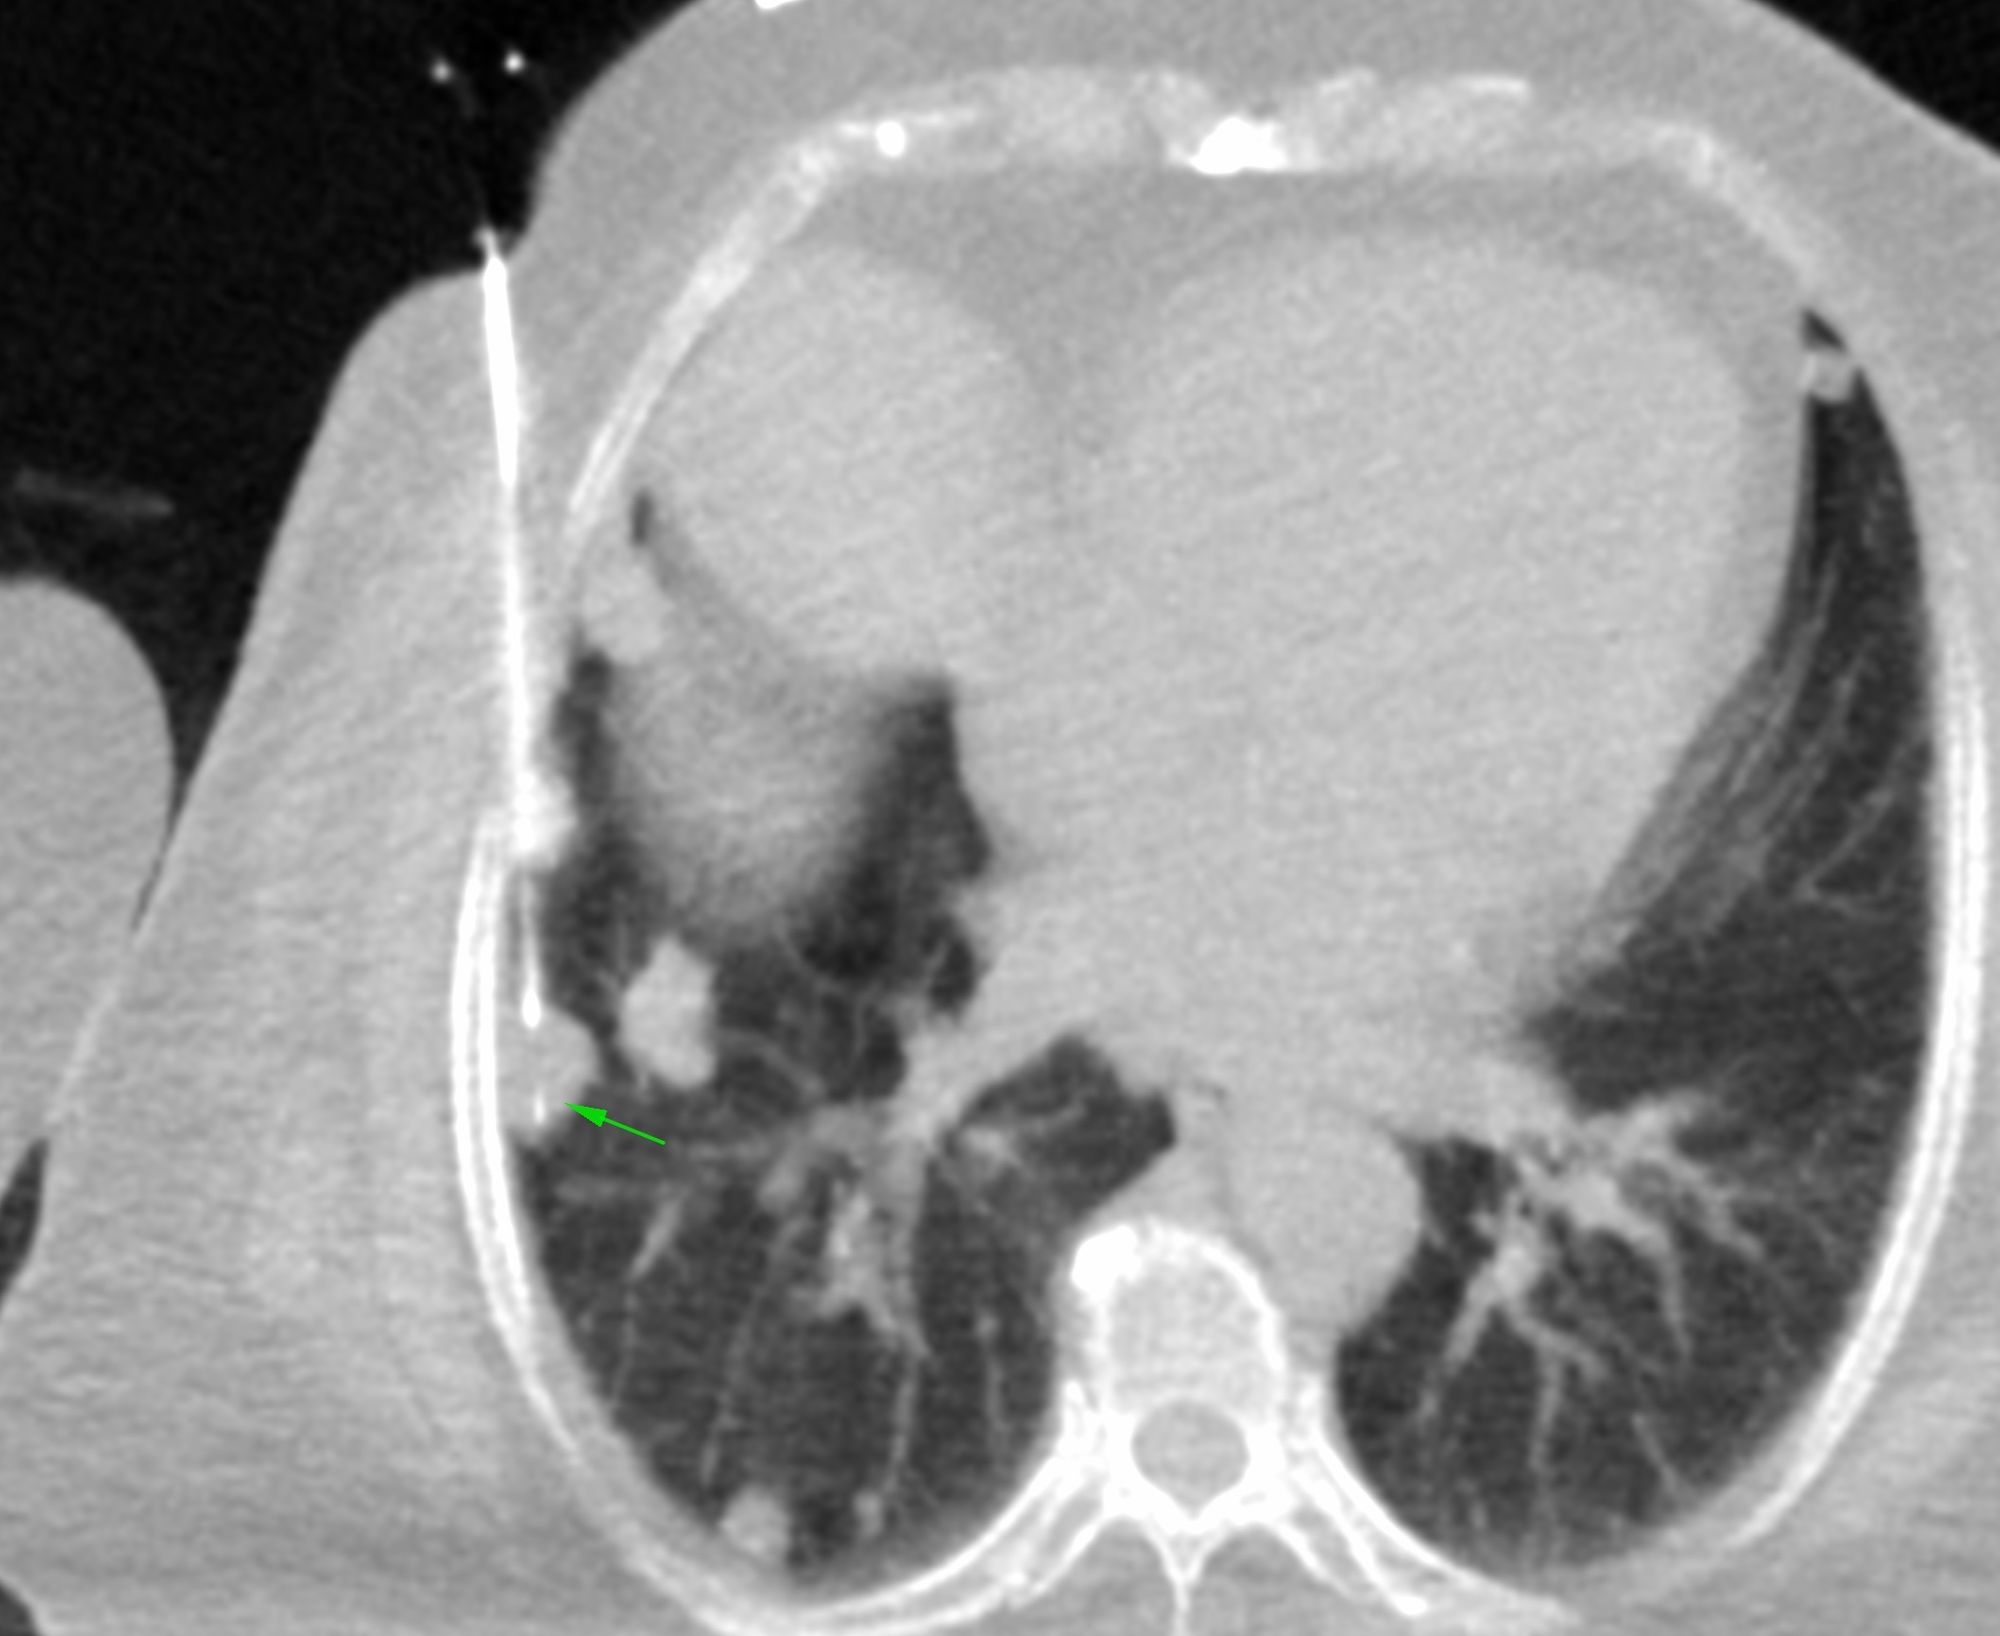

Case 17: 15 mm Lung Nodule Biopsy - Multiple Lung Nodules